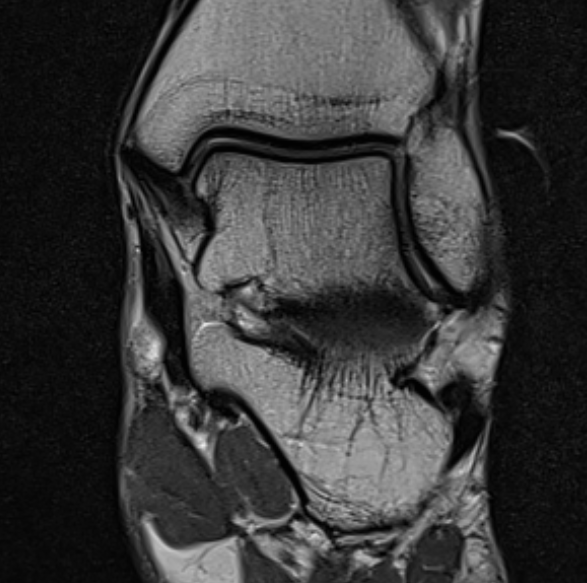

MRI

Old bony avulsion of deltoid ligament